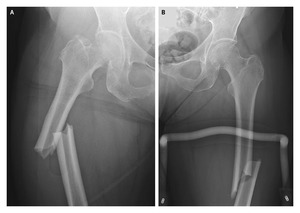

Au mois de mars 2008 paraissait dans le New England Journal of Medicine (NEJM) un article intitulé Atypical Fractures of the Femoral Diaphysis in Postmenopausal Women Taking Alendronate (« Fractures atypiques de la diaphyse fémorale chez des femmes ménopausées traitées par alendronate [Fosamax] »).

« L’innocuité de l’usage à long terme des bisphosphonates dans le traitement de l’ostéoporose a été mise en doute. Deux séries de cas suggèrent l’existence d’un lien entre un traitement prolongé par bisphosphonates et des fractures atypiques. Dans l’une de ces séries, un nombre restreint de patientes a subi des fractures non vertébrales à basse énergie [survenues dans des conditions peu ou pas traumatiques], alors qu’elles étaient sous alendronate à long cours. Dans trois cas, il s’agissait de fractures de la diaphyse fémorale [1]. Les biopsies osseuses faites chez ces patientes ont mis en évidence une inhibition sévère du turnover osseux ainsi que le retard ou l’absence de consolidation des fractures. Dans l’autre série de cas, neuf femmes prenant de l’alendronate au long cours ont présenté des fractures sous-trochantériennes [2].

L’une des études mentionnées par le NEJM est celle parue en mars 2007 dans le Journal of Bone and Joint Surgery : Subtrochanteric insufficiency fractures in patients on alendronate therapy: a caution (« Fractures sous-trochantériennes d’insuffisance chez des patients traités par alendronate: une mise en garde »).

Une autre équipe américaine publie dans le numéro de mai/juin 2008 du Journal of Orthopedic Trauma une étude rétrospective de patients  admis dans un centre d’orthopédie entre 2002 et 2007 : Low-Energy Femoral Shaft Fractures Associated With Alendronate Use (« Des fractures à basse énergie de la diaphyse fémorale liées à la prise d’alendronate »).

Des cas similaires de fractures atypiques sont rapportés par deux autres équipes dans des lettres adressées au NEJM et parues le 17 juillet 2008 sous le titre More on Atypical Fractures of the Femoral Diaphysis (« D’autres éléments sur les fractures atypiques de la diaphyse fémorale »). Ces lettres sont en libre accès.

(Radiographie : e-medicine)

La découverte intéressante est que les fractures à basse énergie de la diaphyse fémorale survenant sous Fosamax présentent des caractéristiques particulières, qui ne se retrouvent que chez 2% des patients n’ayant pas prix de Fosamax, soulignent les auteurs de l’article paru dans le Journal of Orthopedic Trauma. Il s’agit d’une fracture transversale dans une zone d’hypertrophie du cortex diaphysaire, chez des patients ayant pris du Fosamax pendant une durée moyenne de 6 ans et 9 mois. Les auteurs parlent eux aussi d’une « suppression excessive du métabolisme osseux, qui réduit les possibilités de réparation [spontanée] des microfissures et crée ainsi le risque de fractures d’insuffisance » ; celles-ci arrivent par la « propagation d’une fracture de stress dont la consolidation est retardée par l’activité diminuée des ostéoclastes ». (Les ostéoclastes sont les cellules responsables de la résorption osseuse, par opposition aux ostéoblastes, qui, eux, créent de la masse osseuse en calcifiant ce qu’ils ont produit).